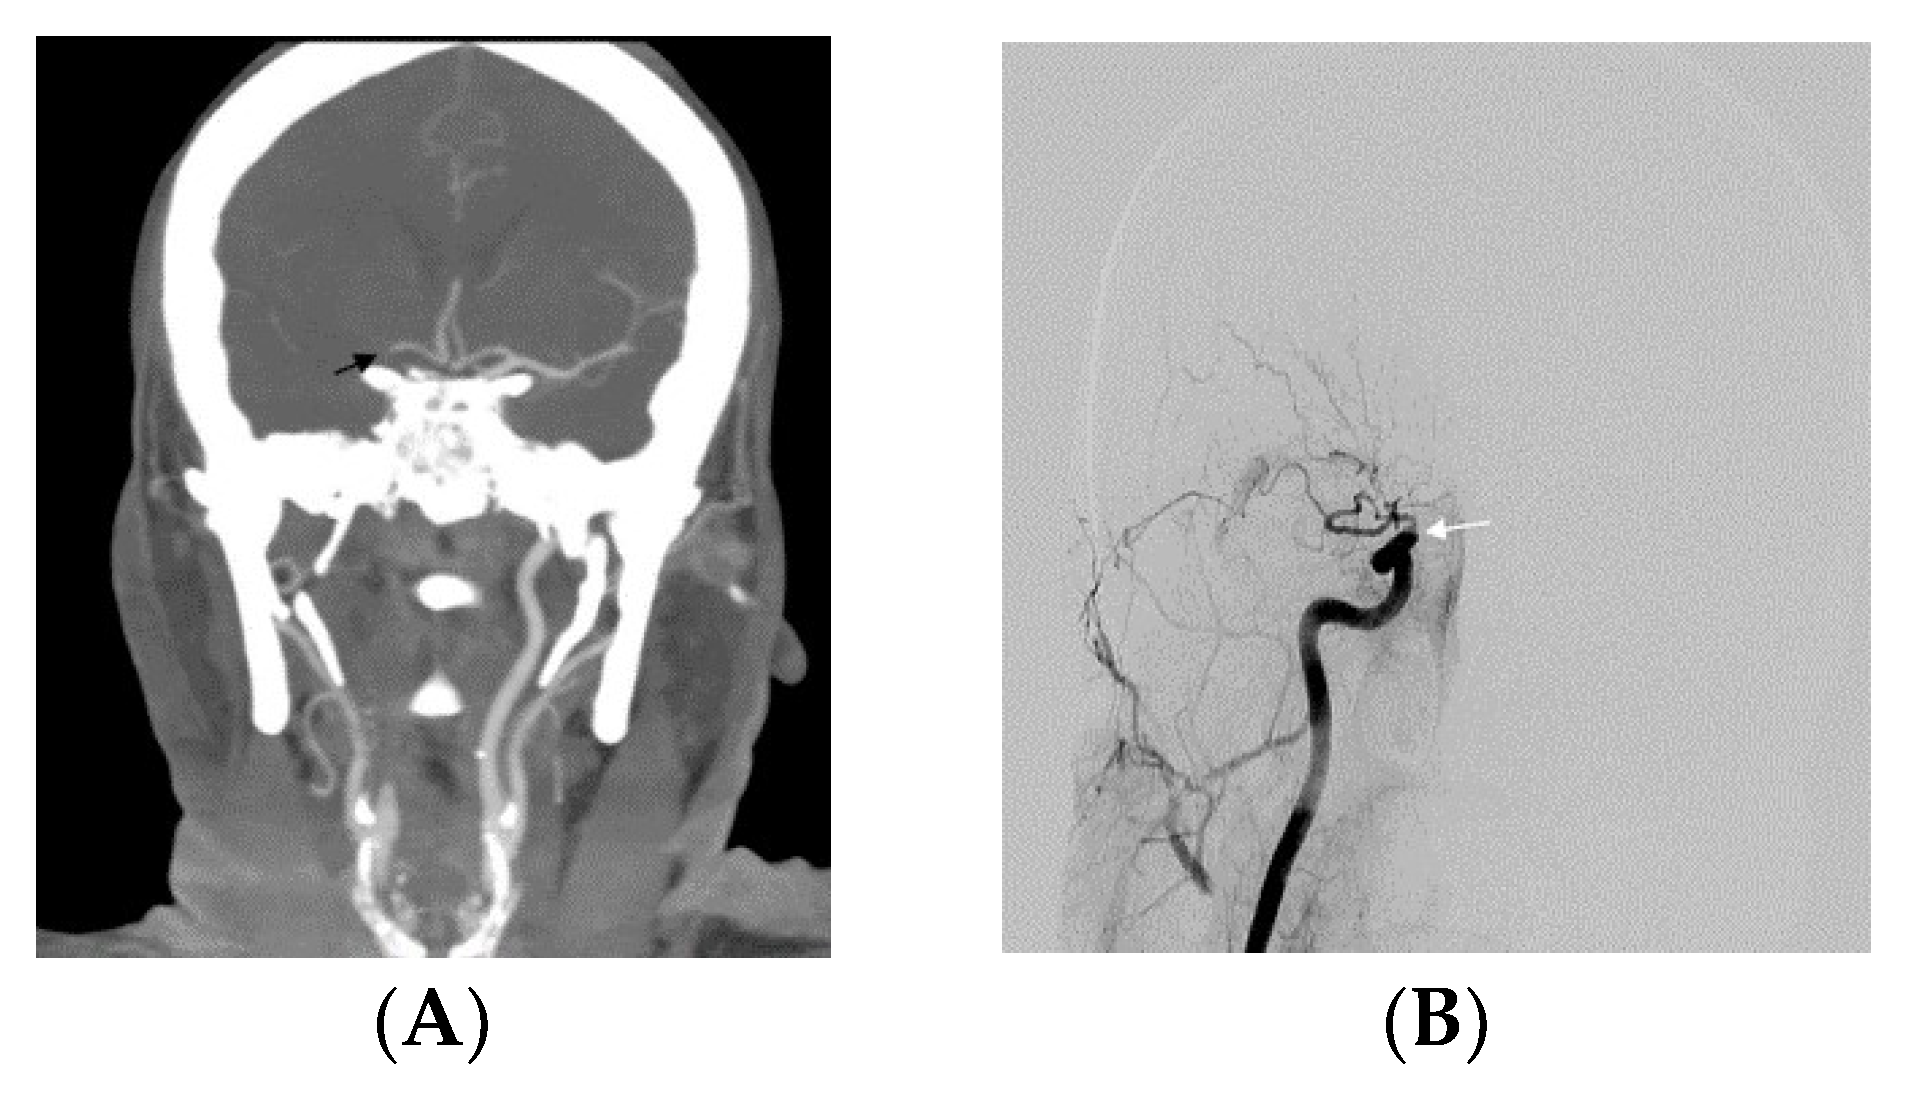

| T occlusion, n (%) | 18 (66.6%) | 26 (68.4%) | 0.881 |

| L occlusion, n (%) | 9 (33.3%) | 12 (31.5%) | 0.881 |